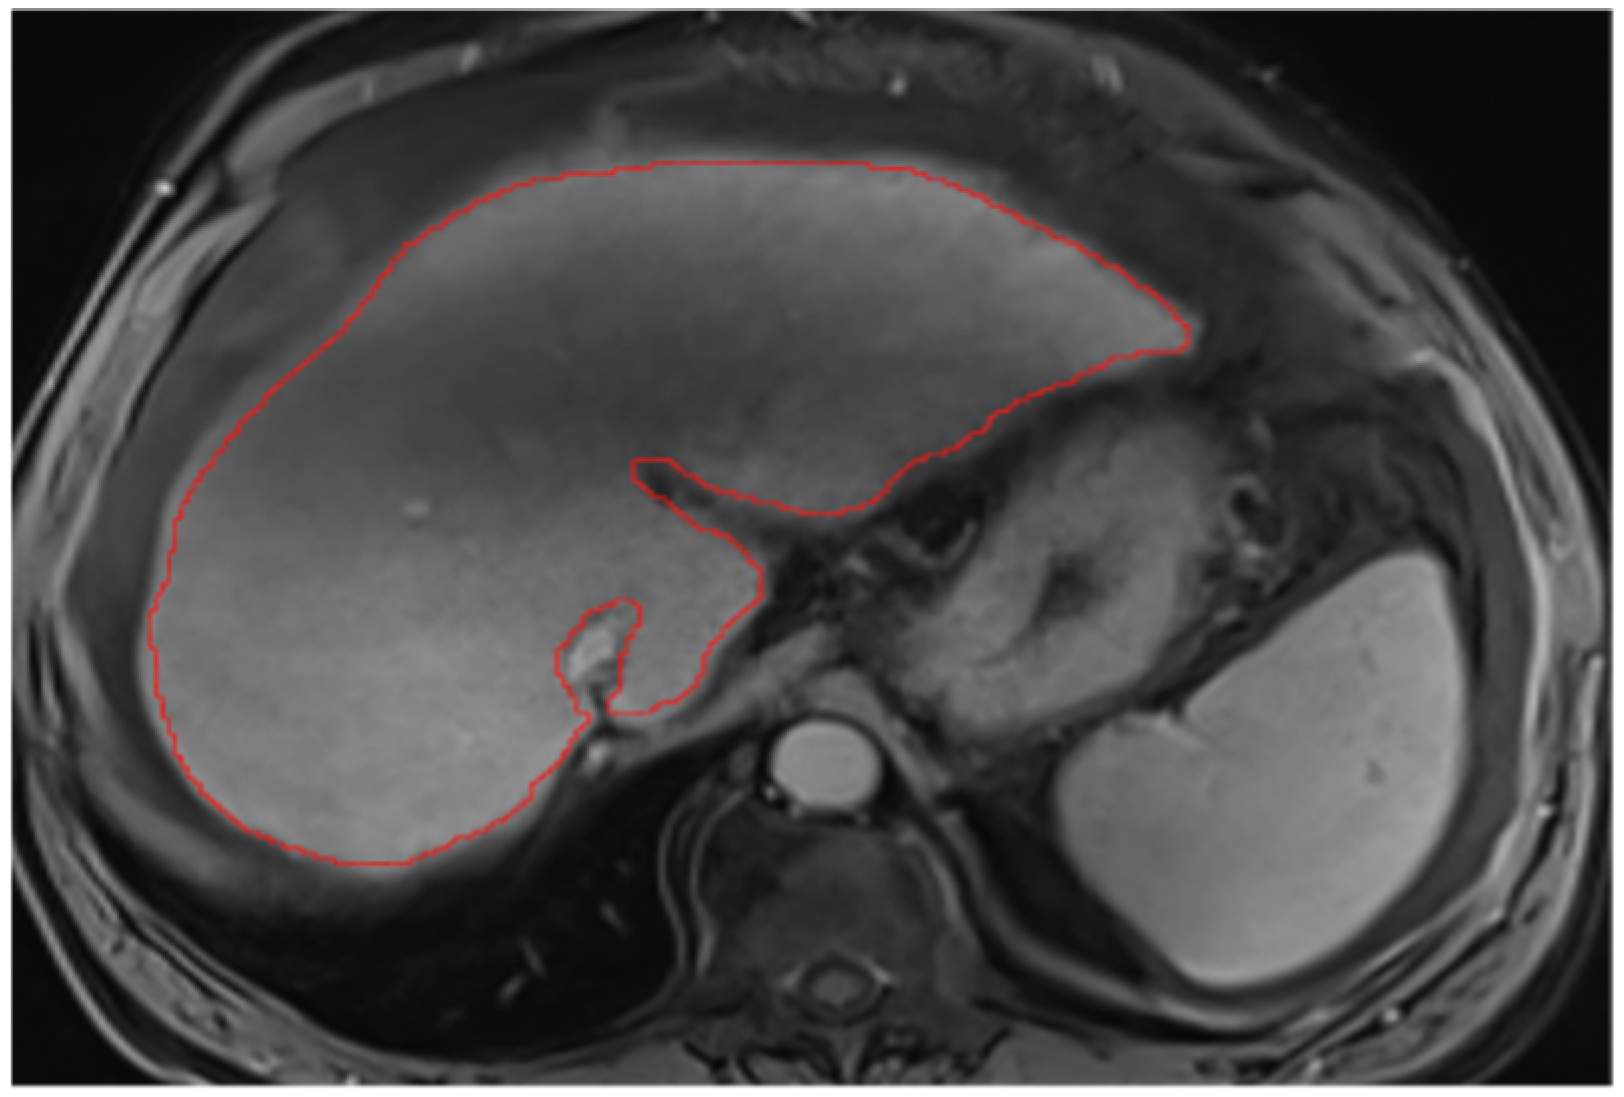

2.2. Liver Segmentations and Protocol

Appendix A.2. Hepatic Hilum Segmentation

Appendix A.3. Vascular Segmentation

Appendix A.4. Ligaments Segmentation